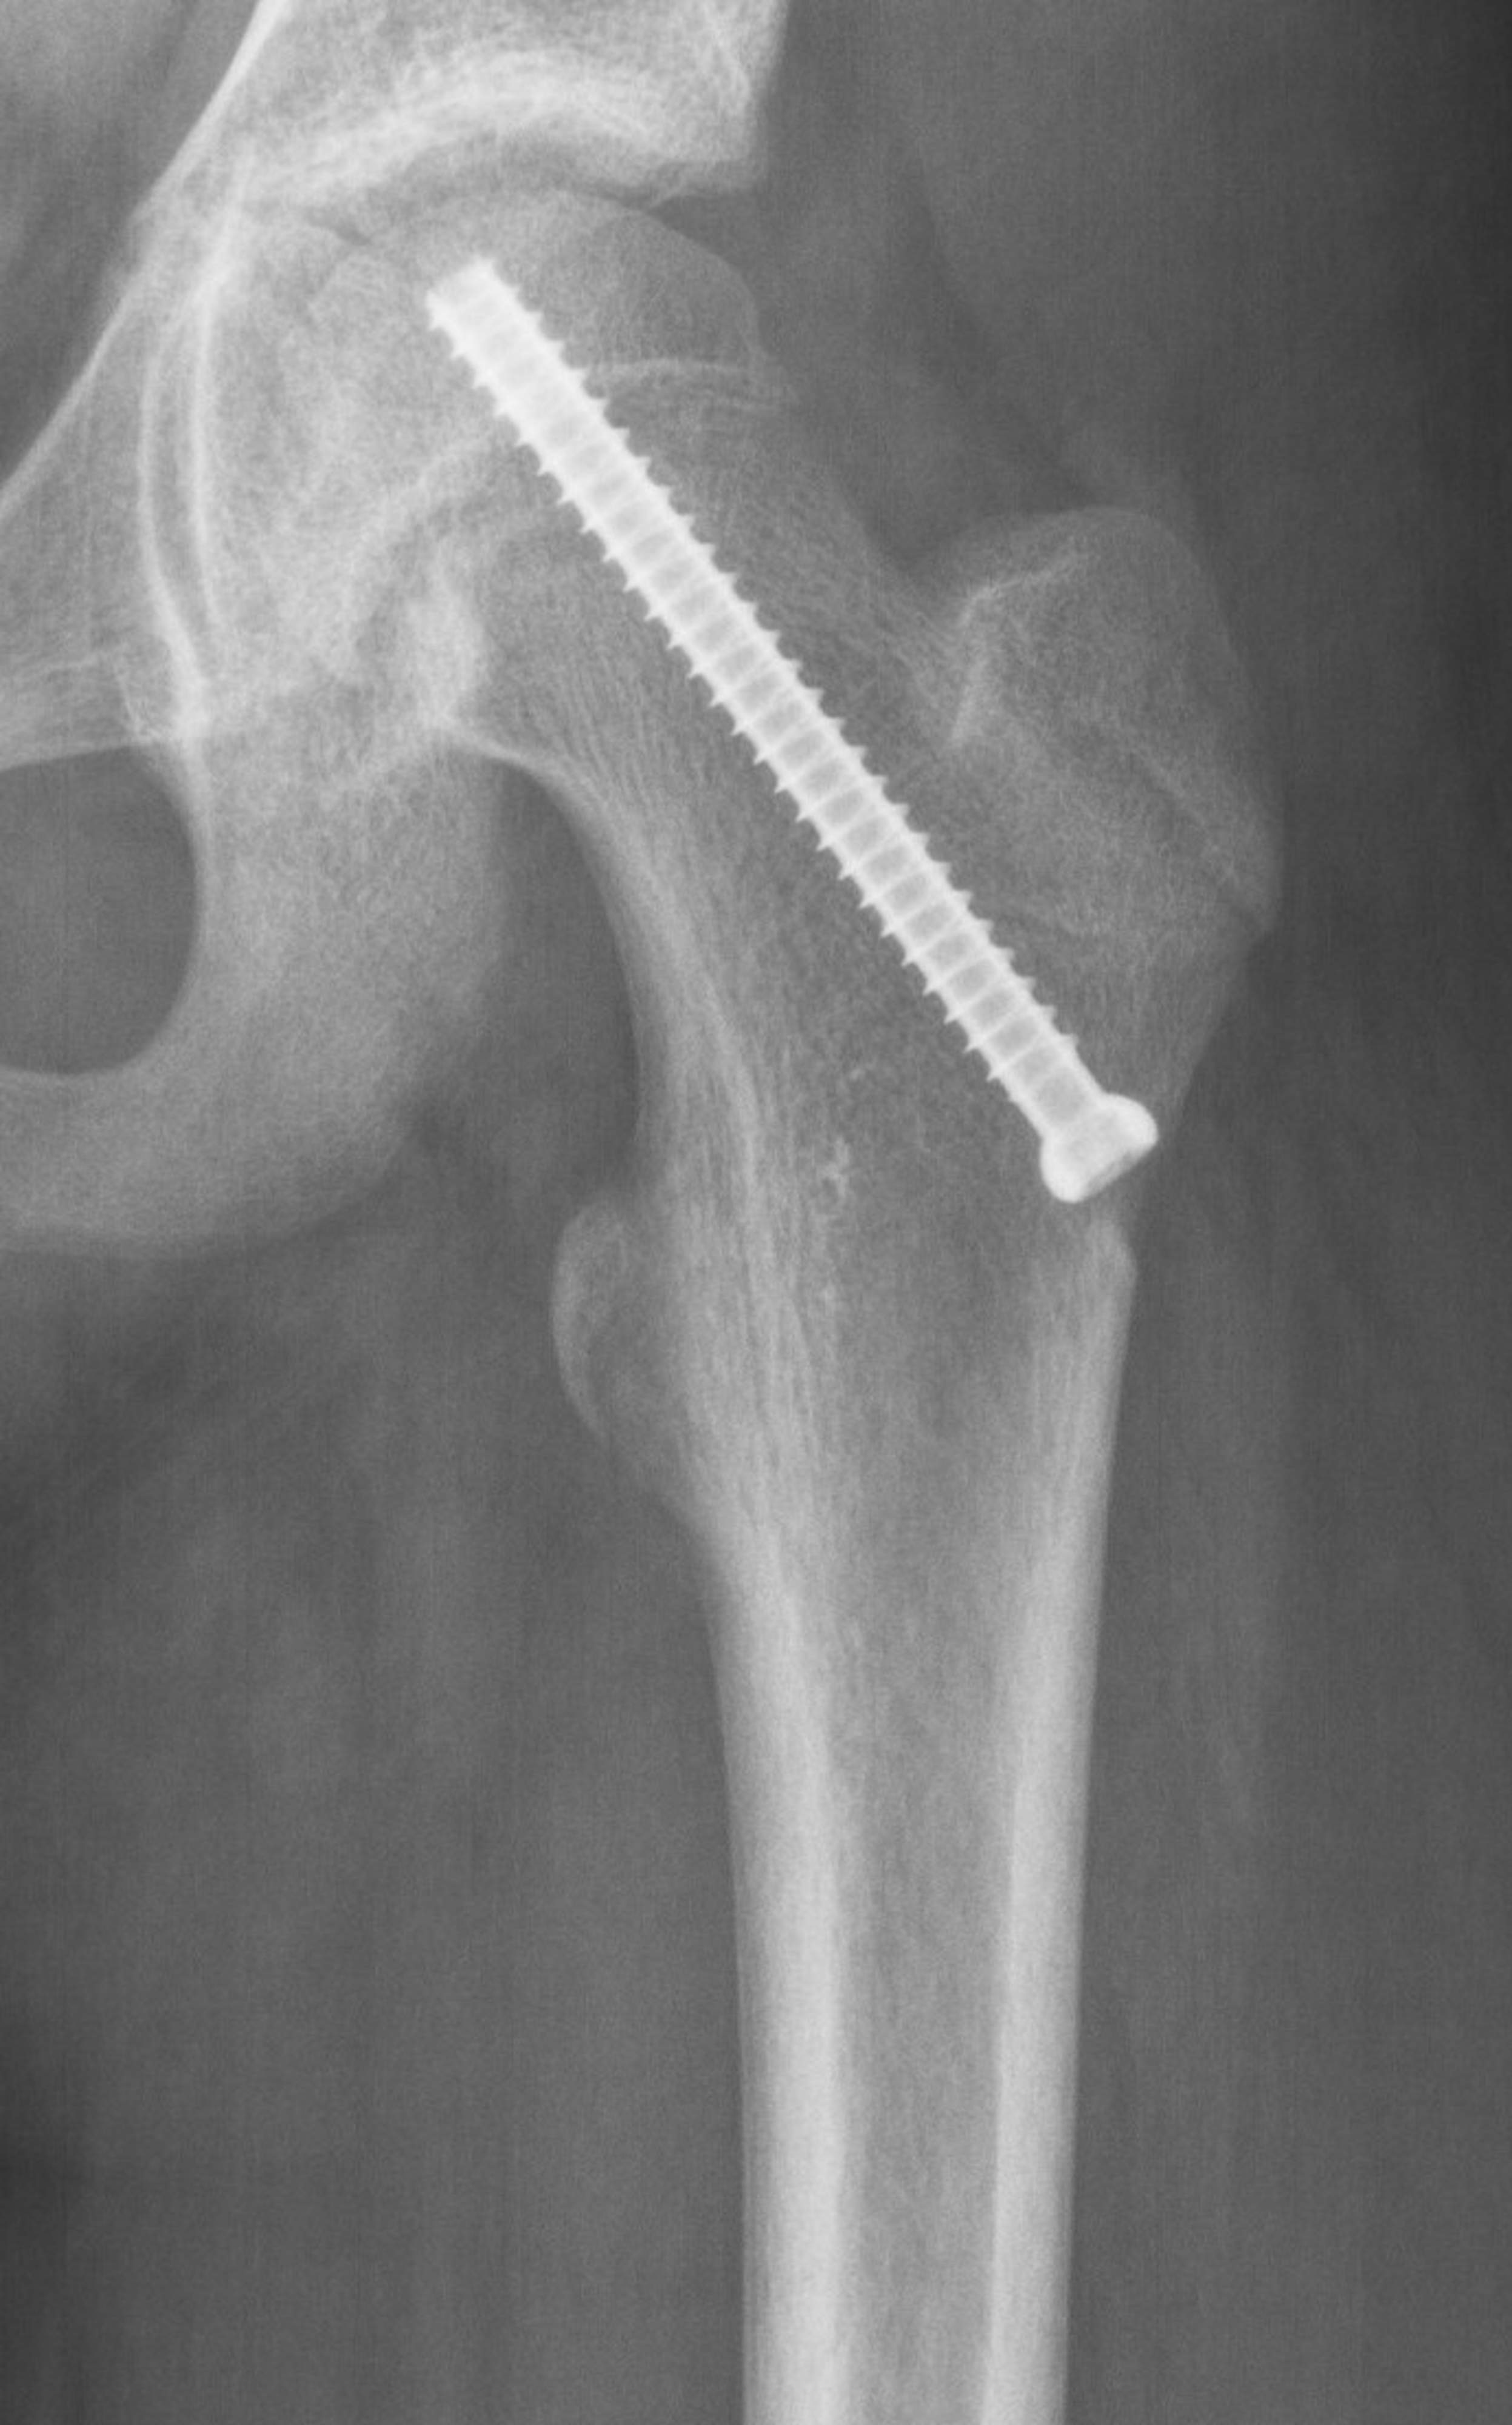

Reisiluun pään liukuma hoidetaan leikkauksella, jossa liukuma kiinnitetään ruuvin avulla estämään siirtymän lisääntymisen. Leikkaushoidon tavoitteena on kiinnittää reisiluun pään siirtymä ja ehkäistä lonkan toimintahäiriöitä ja kulumista. Suuriasteinen reisiluun pään liukuma edellyttää reisiluun yläosan katkaisuleikkausta.